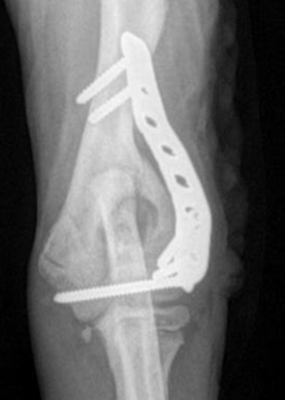

Cette approche chirurgicale réduit significativement le risque de complications ultérieures, notamment en cas d’ossification incomplète ou de fragilité structurelle du condyle huméral. Selon les préférences et l’expertise du chirurgien, il est parfois recommandé d’ajouter une plaque ou une broche au niveau de la crête épicondylaire, renforçant ainsi la fixation et sécurisant davantage la consolidation.

2. Chirurgie après fracture

Si la fissure évolue en fracture, une fixation plus complexe est nécessaire, combinant vis intercondylienne et plaques.